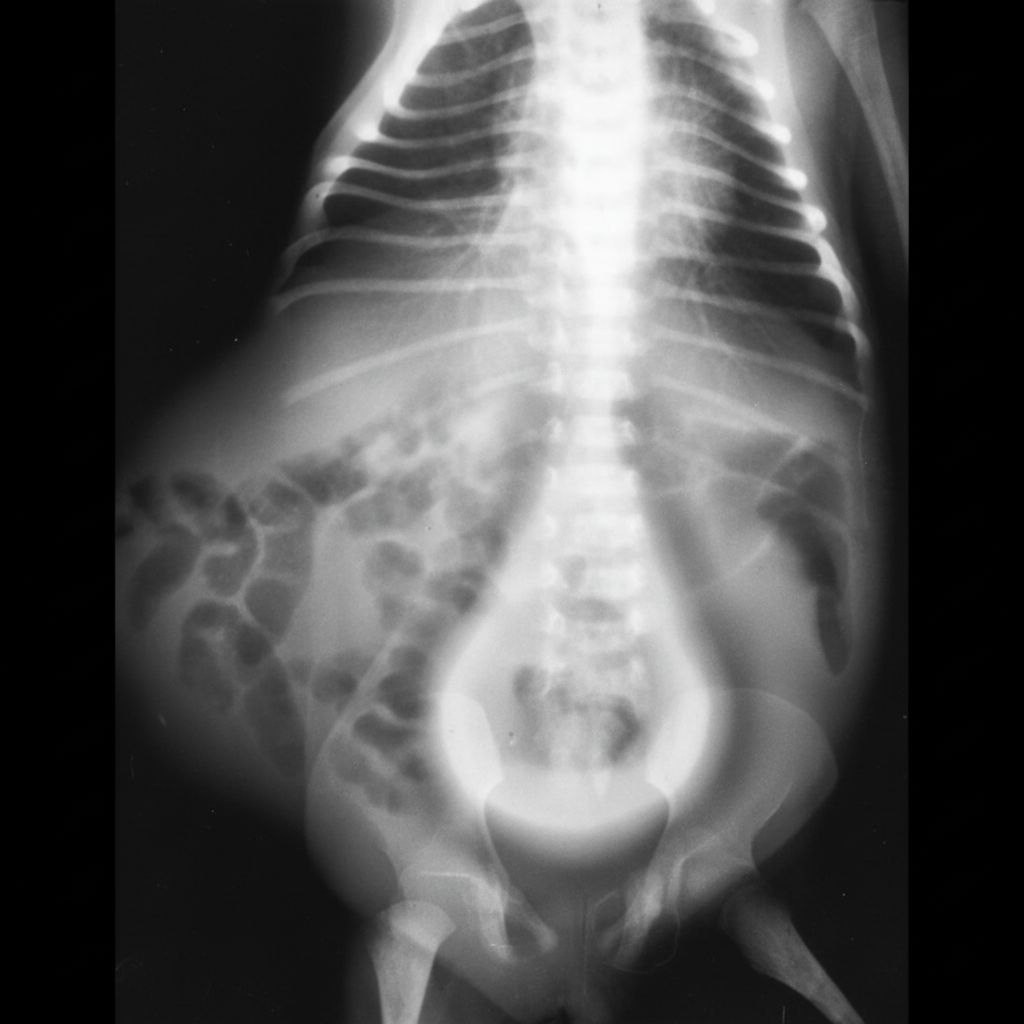

A 56-year-old male presents with burning micturition, increasing frequency, and hesitancy. An intravenous pyelogram was performed, and the radiograph is shown. What is the most likely diagnosis?

Explanation: ***Pelvic lipomatosis*** - Presents with **pear-shaped bladder** and **radiolucent halo** around the bladder on IVP, caused by excess **fatty tissue** in the pelvis compressing the bladder - Commonly affects **middle-aged males** causing **lower urinary tract symptoms** (LUTS) including burning micturition, frequency, and hesitancy due to bladder compression *Multicystic dysplastic kidney disease* - A **congenital condition** typically diagnosed in **infancy or childhood**, not in a 56-year-old male - Shows **multiple non-communicating cysts** replacing normal renal parenchyma on imaging, not the pear-shaped bladder deformity seen here *Aortic aneurysm* - Would present with **pulsatile abdominal mass** and potential **back pain**, not primarily urinary symptoms - IVP would show **lateral displacement** of ureters or kidneys, not the characteristic bladder changes described *Renal cell carcinoma* - Typically presents with **hematuria**, **flank pain**, and **palpable mass** (classic triad), not lower urinary tract symptoms - IVP would show **renal mass effect** or **calyceal distortion**, not the pear-shaped bladder configuration